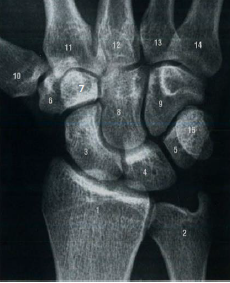

Com base nos seus conhecimentos sobre anatomia dos ossos do carpo, assinale a alternativa que apresenta a adequada correlação.